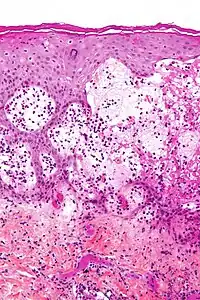

Micrograph of gestational pemphigoid showing the characteristic subepidermal blisters and abundant eosinophils. HPS stain.